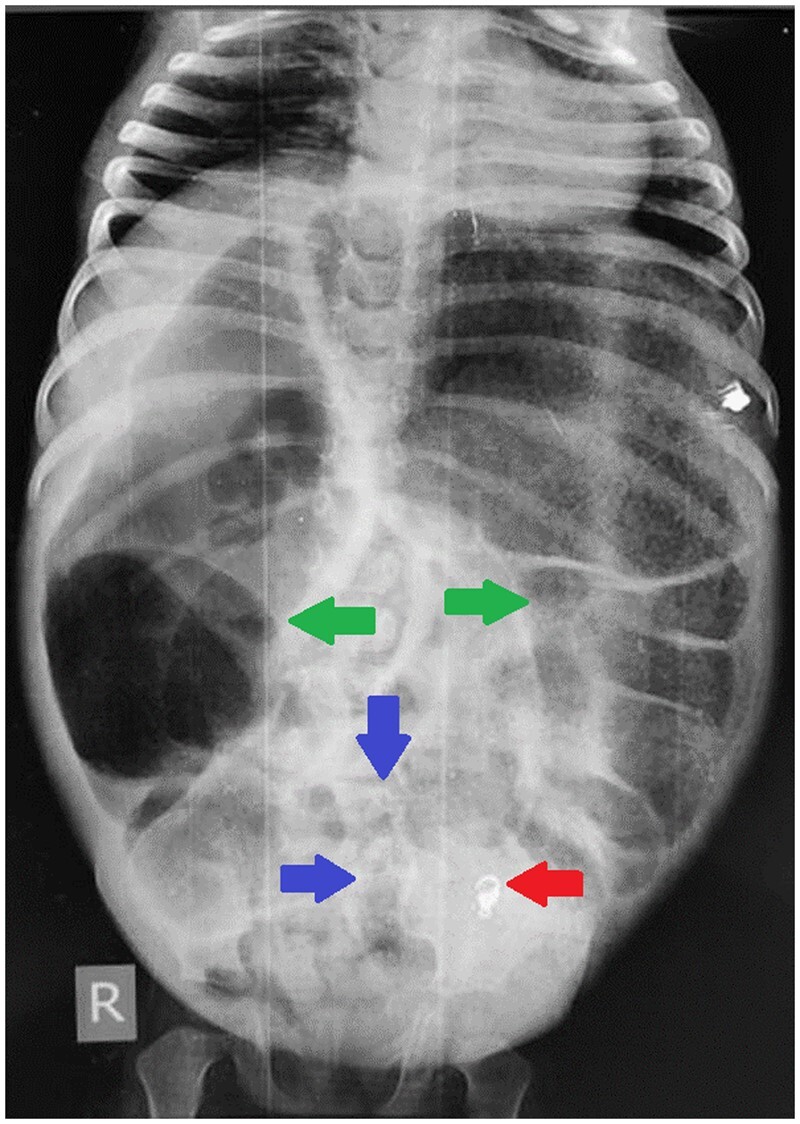

先天性乙状结肠狭窄是一种罕见的疾病,可与赫氏病相似。先天性结肠狭窄通常在出生后几周内出现。我们的病例在 2 岁时出现远端肠梗阻,并伴有慢性便秘、出生后一周内腹部逐渐胀大以及最近一周内胆汁性呕吐的病史。临床诊断为赫氏病。对比增强腹部 CT 显示肠梗阻,过渡点位于乙状结肠近端。乙状结肠近端有一短段狭窄。造影剂灌肠显示乙状结肠近端狭窄。狭窄远端肠道口径正常。手术中也发现了类似的情况。狭窄肠段存在中结肠。切除的狭窄部分在组织病理学中显示有足够的神经节细胞。

Congenital sigmoid colon stenosis is a rare entity that can mimic Hirschsprung disease. Presentation of congenital colon stenosis is usually within first few weeks of life. Our case presented with features of distal bowel obstruction at 2 years of age with the history of chronic constipation and progressive abdominal distention from first week of life and bilious vomiting for the last 1 week. Clinical diagnosis of Hirschsprung disease was made. Contrast enhanced CT abdomen showed bowel obstruction with transition point at the level of proximal sigmoid colon. There was a short segment stenosis at the level of proximal sigmoid colon. Contrast enema showed stenosis at proximal sigmoid colon. The bowel distal to stenosis was normal in calibre. Similar findings were seen during surgery. Mesocolon was present in stenosed segment of the bowel. The resected stenotic segment showed adequate ganglion cells in histopathology.